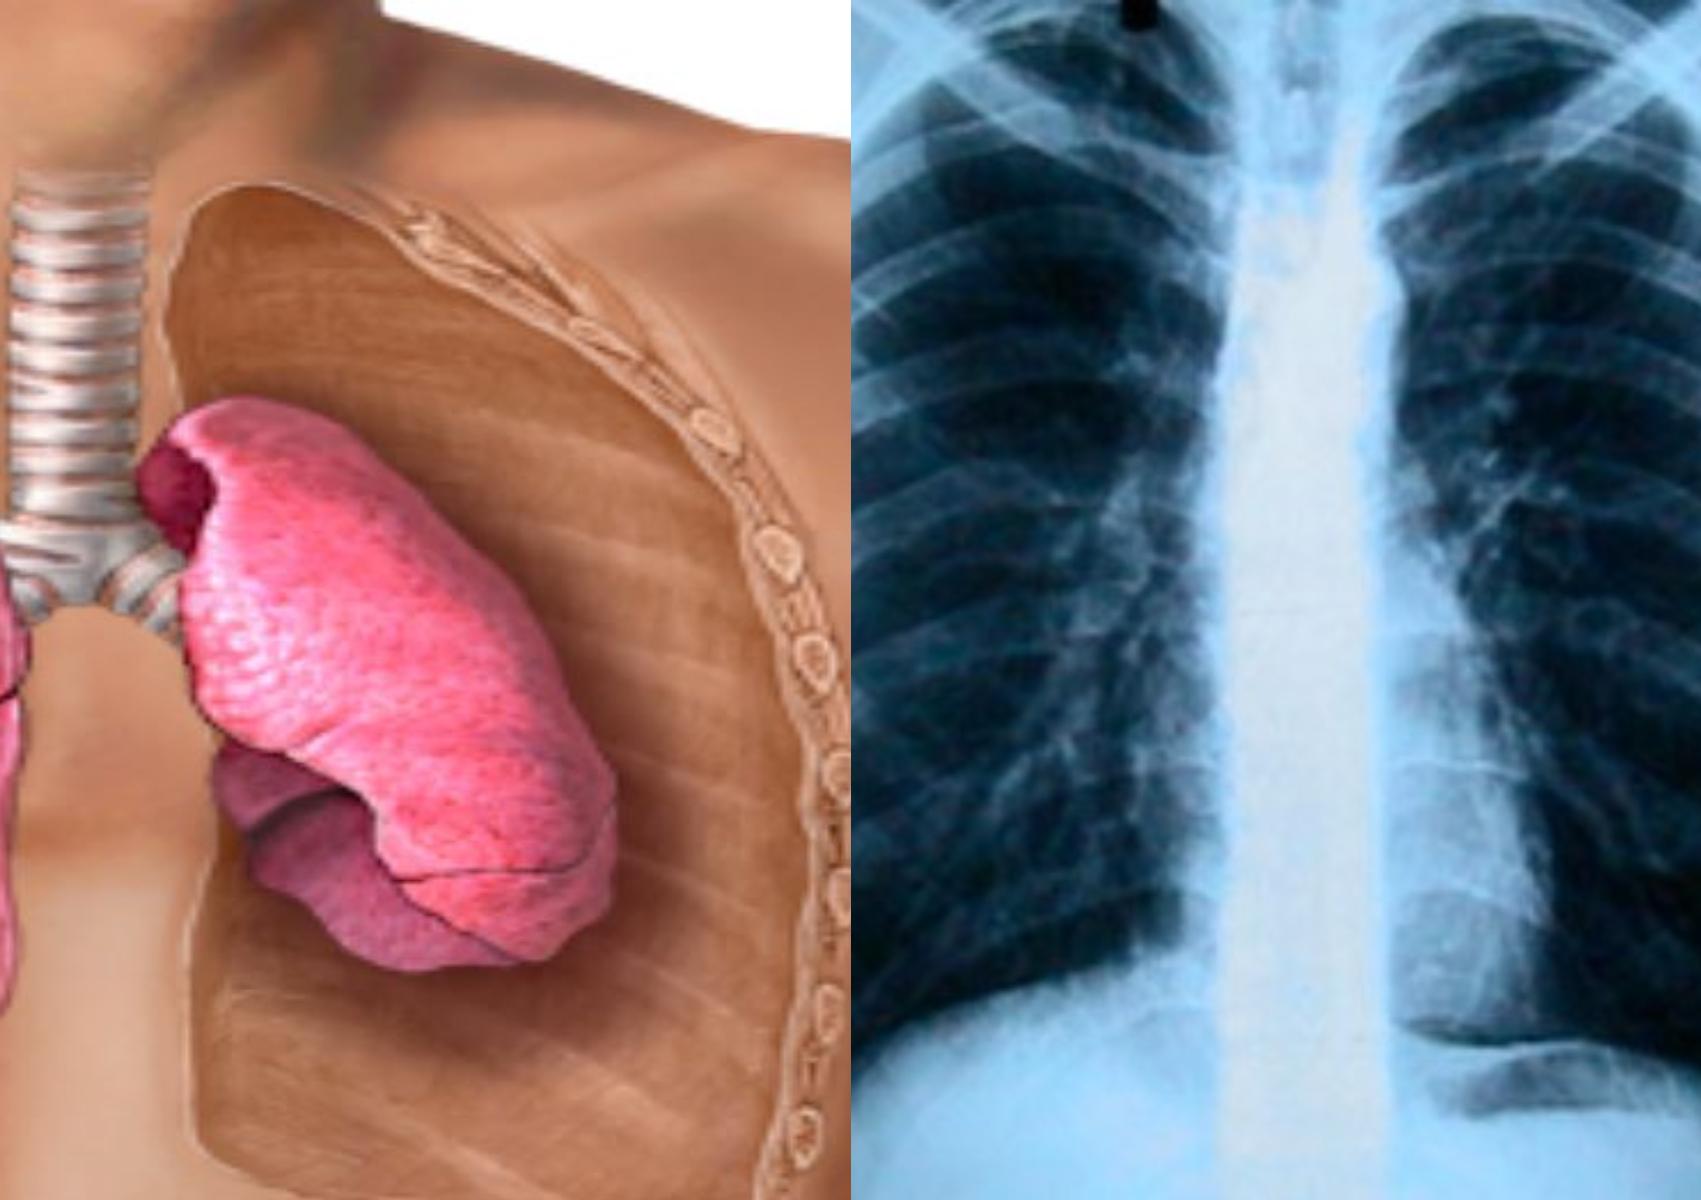

ΥΓΕΙΑ 20.02.25 Πνευμοθώρακας : Όταν ο αέρας από τους πνεύμονες πηγαίνει στον θώρακα – Τα αίτια και οι κίνδυνοι

ΥΓΕΙΑ 17.09.24 Δύσπνοια και πρησμένοι λεμφαδένες: Ποια τα αίτια τα συμπτώματα και η θεραπεία της Σαρκοείδωσης

ΥΓΕΙΑ 14.10.21 Υγρό στον πνεύμονα: Πότε η δυσκολία στην αναπνοή αποτελεί σύμπτωμα και πως επηρεάζει την καρδιά